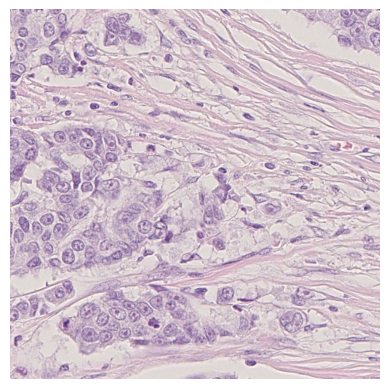

We also analyse the activation maps for each model using GradCAM as described in section S3. This offers more insight into the areas of the image which are contributing most heavily to the models’ representations. In Figure 4(b) we present some representative examples, however, a larger selection which was chosen at random is presented in Figures S10 to S25. The larger selection makes it easier to see the emergent patterns, including that privileged Siamese models tend to mainly identify features which are strongly present in both inputs, while unprivileged Siamese models tend to learn more diffuse features that are not specific to one cell phenotype or image region. TriDeNT ♆ incorporates both sets of features, learning both features specific to the privileged data and more the general features associated with unprivileged Siamese networks.

We can see in Figure 4(b) panel A that for ERG, the privileged Siamese model focuses almost exclusively on any nuclei which could be endothelial cells. As there are very few endothelial cells in the dataset, it could be an effective strategy to identify anything that could potentially be an endothelial cell to minimise the difference between the representations of the H&E model and the IF mask model. In the corresponding unprivileged Siamese image, we see that the model identifies some of these nuclei, albeit less strongly, but also focuses heavily on the other tissue and even the background, while strongly fixating on two spots of debris in the center of the image. This model has less ‘incentive’ to learn the weak features related to endothelial cells as these occur rarely and are not easy to detect, while more generic strong features such as the presence of connective tissue and the prevalence of background are more common and predictable from augmented images. We see that TriDeNT ♆ combines these two feature sets, strongly identifying nuclei while also identifying the connective tissue.

In panel C we see a similar pattern, with the privileged Siamese model fixating solely on the nuclei, while the TriDeNT ♆ model takes a more balanced approach. The unprivileged Siamese model appears to focus on a single cluster of nuclei while neglecting others, and similarly identifies an area of fibroblasts with its distinctive pattern but does not others.

In contrast to panels A and C which represent models with poor privileged Siamese results, panels B and D represent models whose privileged Siamese results were comparable to both TriDeNT ♆ and even the supervised baseline. It is therefore interesting to note that there are far more similarities between the privileged Siamese and TriDeNT ♆ models in both cases. Particularly in panel B, TriDeNT ♆ and the privileged Siamese model return virtually identical heatmaps, with both strongly identifying epithelial nuclei and neglecting the same areas of connective tissue. The unprivileged model in this case appears to focus solely on the centre of the image, giving a significantly different heatmap to the other panels.

Panel D again shows the previous pattern, with the privileged Siamese model identifying the features strongly present in the privileged data – fibroblasts – while neglecting the nuclei present. TriDeNT ♆ also strongly identifies the connective tissue, but, unlike the privileged Siamese model, does not completely neglect the nuclei. The unprivileged Siamese model primarily identifies background, and does not appear to identify the nuclei in this example.